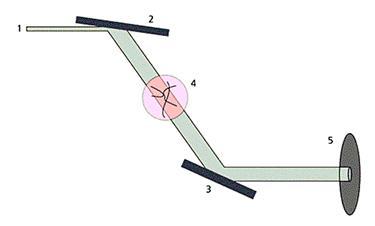

Рис. 1. Схема установки на Курчатовском источнике СИ, иллюстрирующая метод рефракционного контраста. 1 - падающий пучок СИ, 2 - кристалл-монохроматор, настроенный на отражение (511), 3 - кристалл-анализатор, регистрирующий отражение (333), 4 - исследуемый объект, 5 - регистрирующее устройство (детектор на основе ПЗС-матрицы).

Для получения изображений по методу рефракционной интроскопии объект помещается внутрь специального прибора, состоящего из двух совершенных кремниевых кристаллов (рис.1). Первый кристалл служит монохроматором излучения, второй - анализатором.